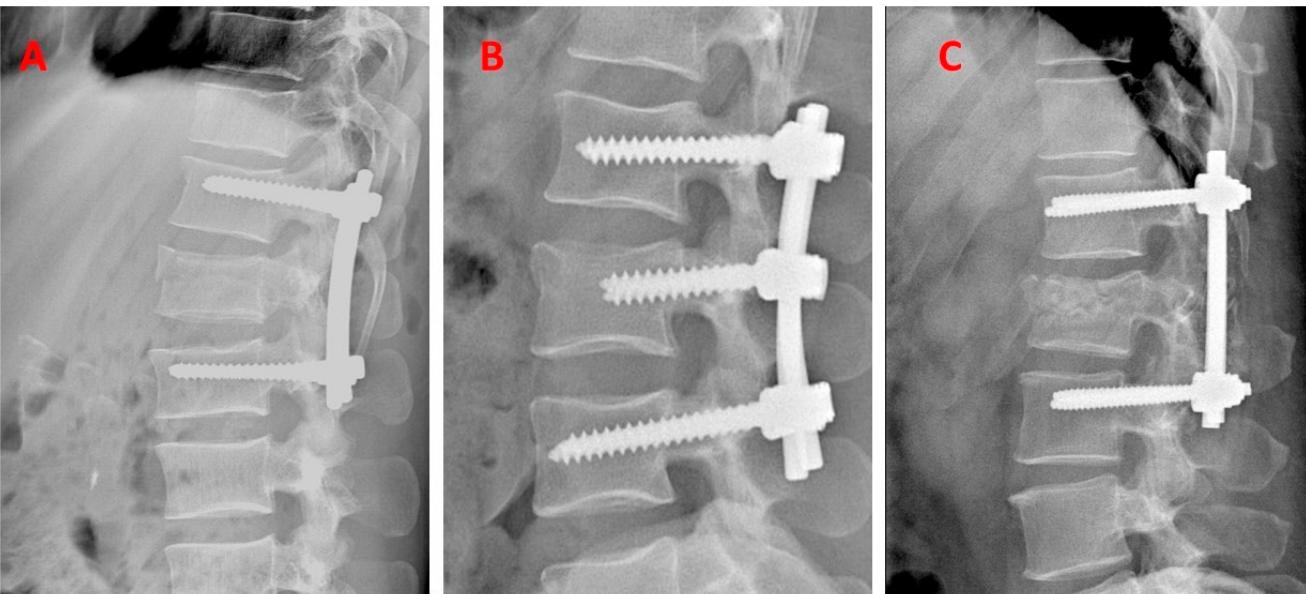

Surgical Fixation Techniques

Surgical Management

Indications:

- Unstable with/without neurological injury

- Progressive neurological deficits

Stabilization Methods:

- Skin/Skeletal traction

- Surgery ± Decompression